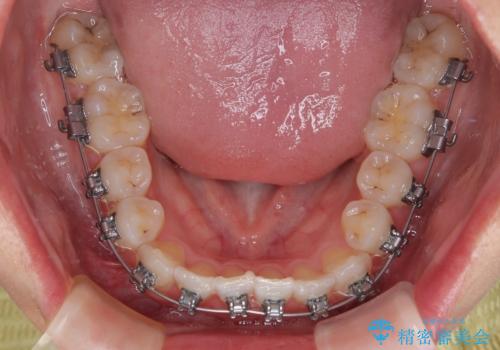

前歯のクロスバイト 裏側に隠れた歯をワイヤー装置で短期間治療

- 矯正装置

- メタルブラケット

- 上顎前歯のクロスバイトを気にして来院された患者様です。

ワイヤー矯正でもマウスピース矯正でも対応可能でしたが、マウスピースによる自己管理に一切の自信がないとのことで、ワイヤー装置にて矯正治療を行うこととしました。

装置の外見を気にしていましたが、短期間で治療を終えることができるだろうと伝えると、安価であるメタルブラケットを選択されました。

想定通り、1年強で綺麗に仕上げることができました。